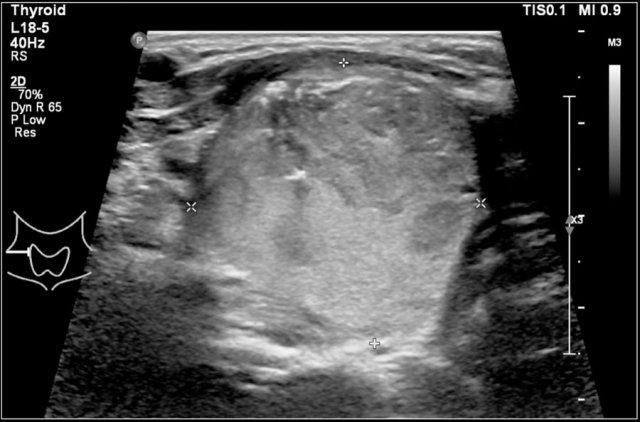

Đây là hình ảnh của một bé gái 16 tuổi mắc cường giáp.

Tuyến giáp to lan tỏa với tình trạng sung huyết.

Chẩn đoán cuối cùng là bệnh Graves.

Bệnh nhân được điều trị bằng I-131.

Trong bệnh Graves, tuyến giáp cũng to ra và cho thấy sự tăng tưới máu.

Trên siêu âm Doppler màu, hình ảnh này được mô tả như một địa ngục lửa với màu đỏ và xanh.